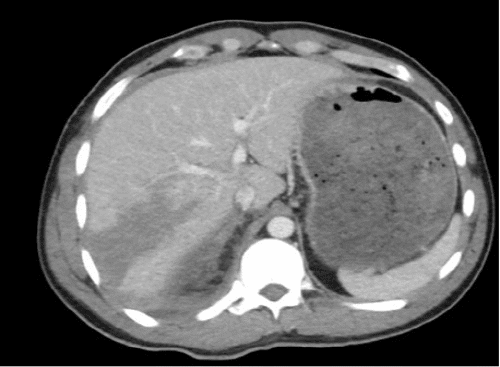

A 31-year-old male trauma transfer from another hospital sustained blunt abdominal trauma following a snowboarding accident. The referring hospital's CT scan revealed a liver laceration (grade IV), extensive right kidney injury (grade IV) with a perinephric hematoma, possible damage to the right renal collecting system with extravasation of urine, and a fractured 10th right rib (Figure 1).

Figure 1. Preoperative Imaging Findings. Published with Permission

A) Grade IV liver laceration.

B) Grade IV right kidney injury with perinephric hematoma and possible injury to the proximal ureter (arrow), evident on delayed films.